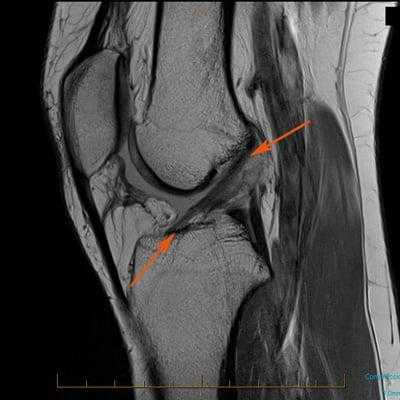

Как травма выглядит на МРТ.

Вместо рентгена можно сделать магнитно-резонансную томографию (МРТ) коленного сустава. Это самый информативный метод диагностики повреждений ЗКС. Он позволяет увидеть мягкие ткани сустава и поставить окончательный диагноз.

На разрыв ЗКС будут указывать следующие признаки: связку не видно, нарушена непрерывность волокон связки или они расположены неправильно. Косвенно о наличии разрыва говорит заднее смещение большеберцовой кости и волнистый контур связки.

Самым информативным методом диагностики ПКС является магнитно-резонансная томография (МРТ) коленного сустава. МРТ позволяет визуализировать мягкие ткани в области сустава и поставить окончательный диагноз [2] .

Признаки разрыва ПКС:

- связка не визуализируется;

- нарушена непрерывность её волокон;

- нетипичное расположение волокон;

- косвенные признаки — связка имеет волнистый контур, большеберцовая кость смещена вперёд, задняя крестообразная связка значительно отклонена назад.